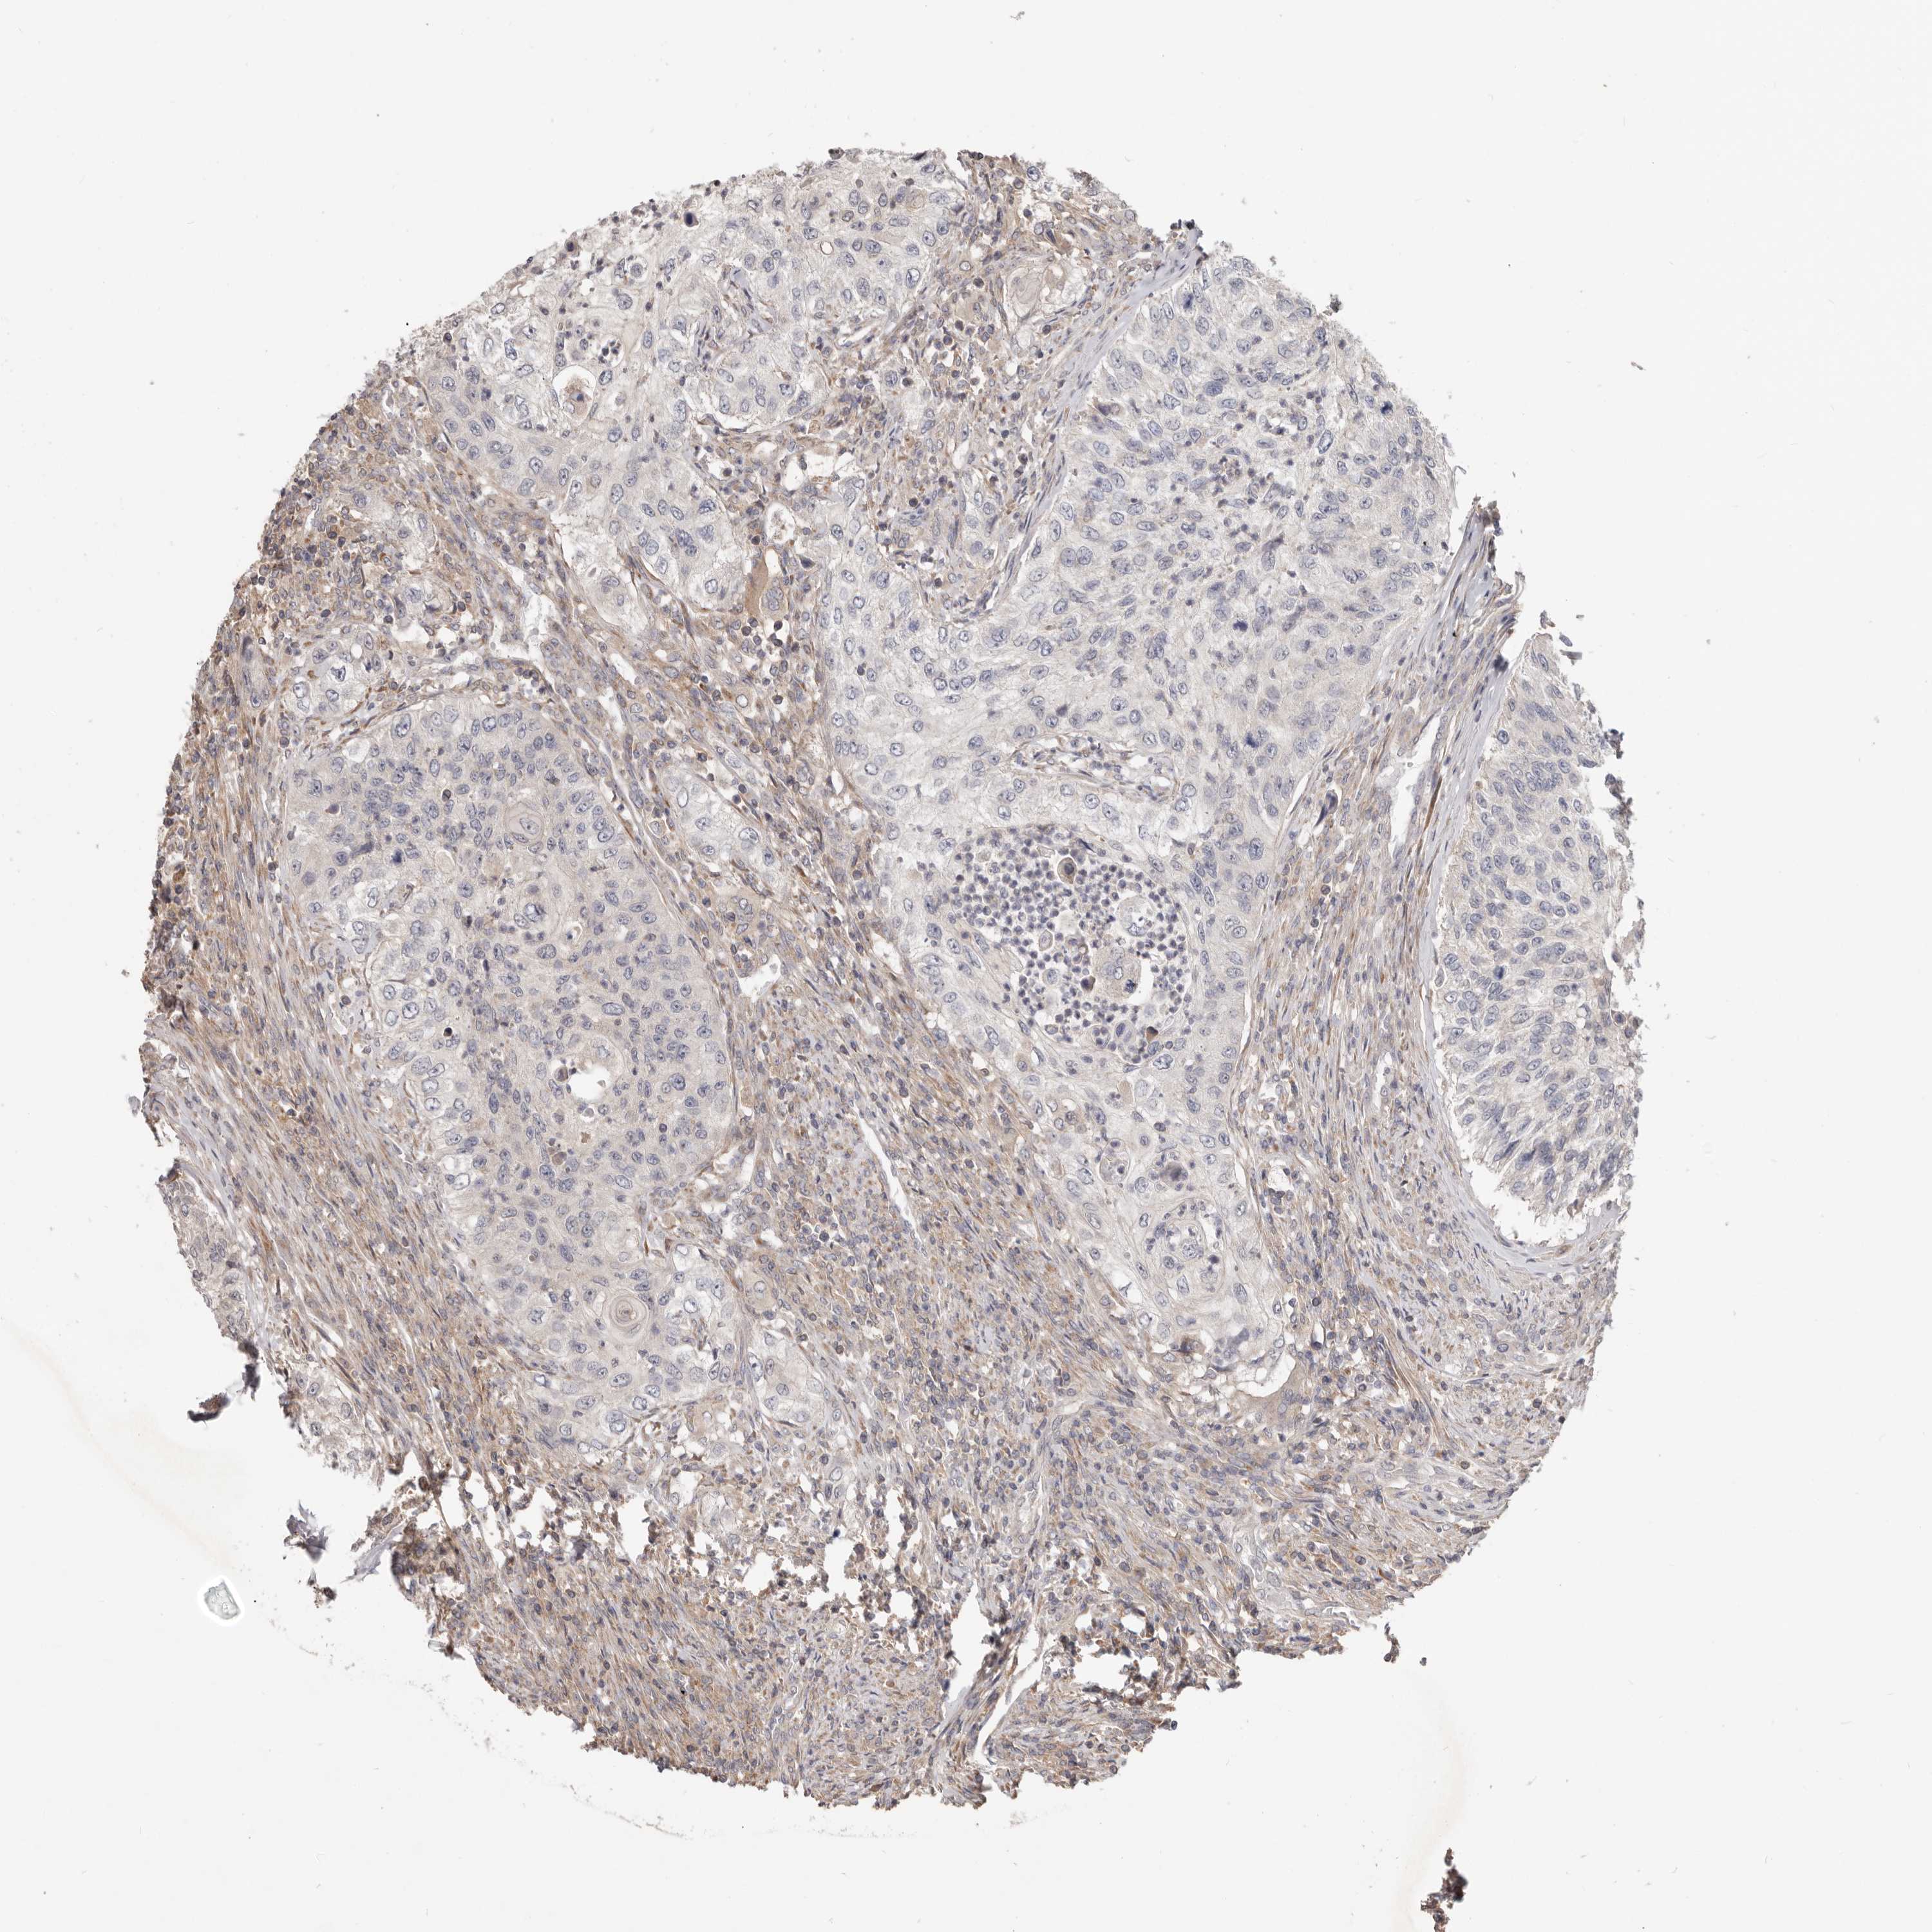

UROTHELIAL CANCER - Protein expressioni

A mouse-over function shows sample information and annotation data. Click on an image to view it in a full screen mode. Samples can be filtered based on level of antibody staining by selecting one or several of the following categories: high, medium, low and not detected. The assay and annotation is described here.

Note that samples used for immunohistochemistry by the Human Protein Atlas do not correspond to samples in the TCGA dataset.

Antibody stainingi

Antibody staining in the annotated cell types in the current human tissue is reported as not detected, low, medium, or high, based on conventional immunohistochemistry profiling in selected tissues. This score is based on the combination of the staining intensity and fraction of stained cells.

Each image is clickable and will lead to virtual microscopy that enables deeper exploration of all samples and also displays staining intensity scores, fraction scores and subcellular localization as well as patient and tissue information for each sample.

Antibody HPA029925

Antibody CAB004490

Urothelial carcinoma, Low grade

Urothelial carcinoma, High grade